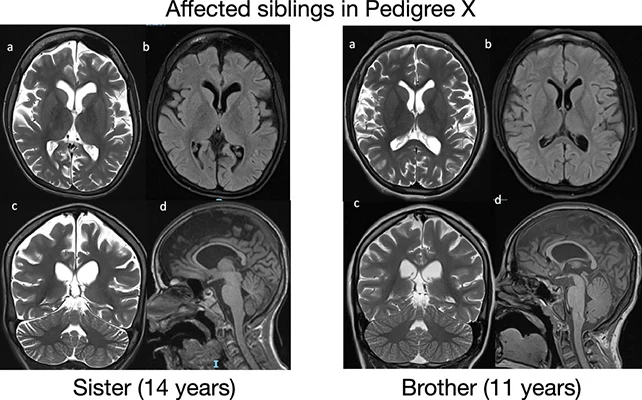

With an estimated prevalence suggesting that ReNU2 syndrome may account for approximately 10 percent of neurodevelopmental disorder cases with a known genetic, recessive origin—potentially affecting thousands of individuals in the UK alone—the researchers indicate that its presentation can include developmental delays, restricted verbal capacity, and diminished muscle tone.

Learning impairments might be apparent, alongside characteristics resembling those seen in autism spectrum disorder and difficulties with ambulation or other forms of motor function. While epilepsy or challenges with respiration and feeding may be involved, the condition appears to manifest uniquely in each affected child.